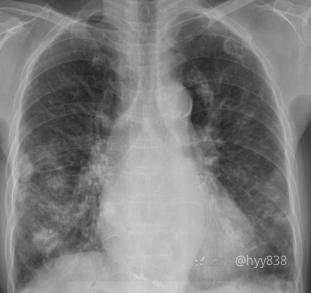

简要病史:59y/F,咳嗽伴胸部不适半年,既往史:肛门癌、SLE(系统性红斑狼疮)、狼疮性肾炎

胸部CT